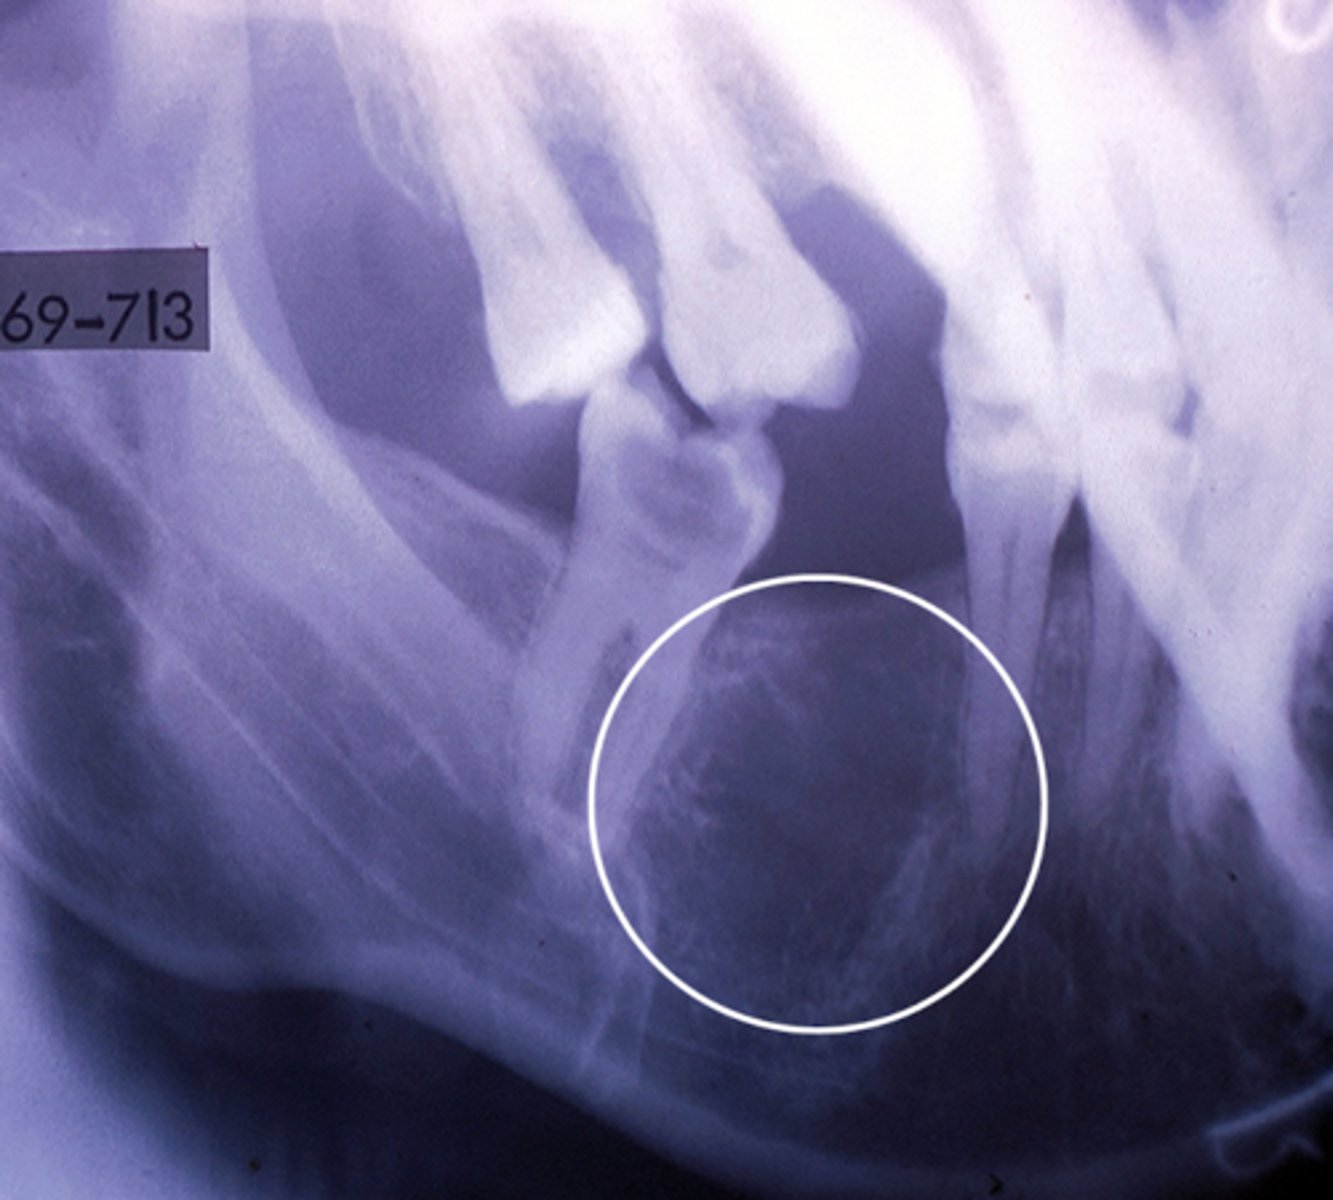

Cleidocranial dysplasia

- Lack of clavicles

- Many supernumerary, impacted teeth